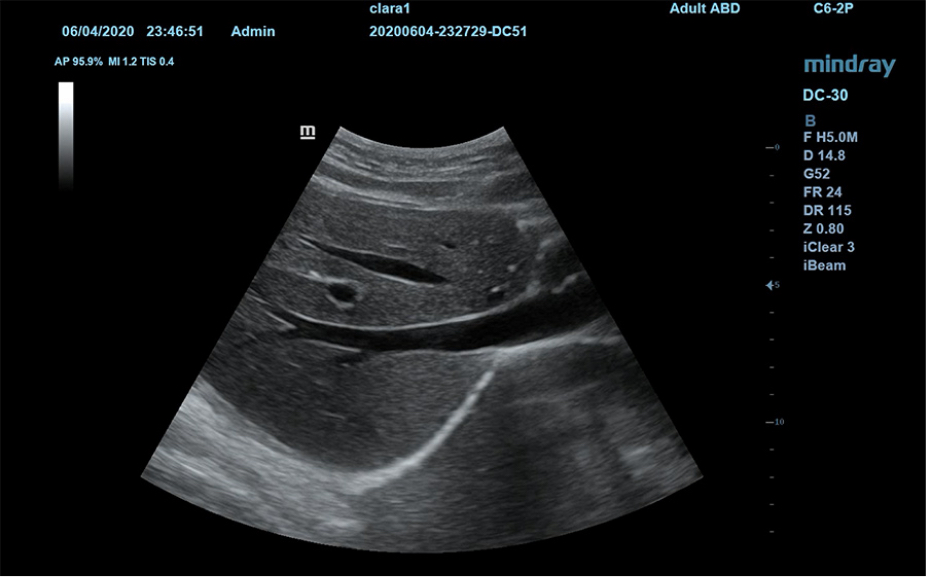

1Ruime keuze aan toepassingsspecifieke onderzoeksvlakken

Vlakpakketten voor verschillende toepassingen: Abdomen, verloskunde/gynaecologie, schildklier, borst, testikel.

Inclusief verschillende (meervoudige) beeldmodi.

Anatomische illustraties

2

Normale anatomische illustraties met inbegrip van schematische beelden en ultrasoundbeelden.

Zijdelingse weergave van een standaard ultrasonogram dat visuele aanwijzingen geeft over de relevante gebieden.

Standaard ultrasoundbeelden

3

Vergelijking realtimescan ter referentie.